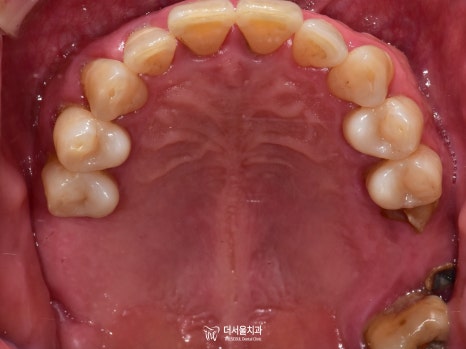

3) 교합면

발치를 하셨기 때문에 텅 비어 있는 곳이 많았습니다.

하악 전치부 쪽이 심각한 것으로 판단이 되네요.

보시다시피 하악 전치부의 문제들이 심각했습니다.

그러나 이쪽에는 또 다른 문제가 있었는데요.

심한 치주 질환으로 공간적으로 뼈가 너무 없었습니다.

즉, 픽스처를 심기에는 어려움이 있다는 뜻이죠.